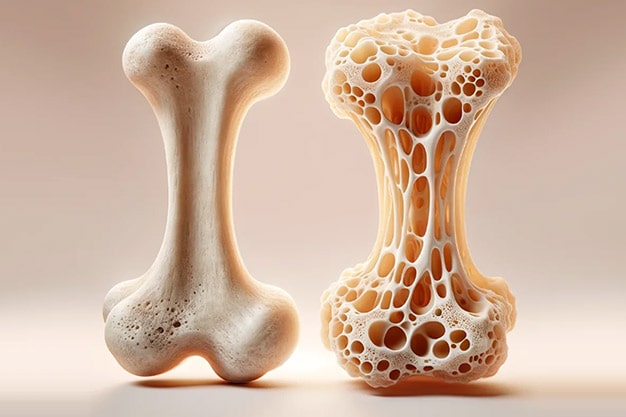

برای آنکه متوجه شویم پوکی استخوان چگونه اتفاق میافتد، باید فیزیولوژی استخوان را به صورت خلاصه بررسی میکنیم. استخوان یک بافت زنده و دائما در حال تغییر است که از یک لایه داخلی و یک لایه خارجی تشکیل میشود. لایه خارجی نازک و متراکم است و لایه داخلی دارای ساختار خانه-خانه و مشابه کندوی زنبور عسل است. بافت استخوان از فیبرهای پروتئینی مستحکم و با خاصیت الاستیکی به نام کلاژن، فسفات کلسیم و مواد معدنی دیگر تشکیل میشود. ترکیب شبکه کلاژن و فسفات کلسیم باعث استحکام و در عین حال انعطافپذیری در برابر ضربات میشود.

زمانی که حفرههای میان شبکهها در لایه داخلی، به علت تحلیل کلسیم بزرگ میشوند، استخوان به تدریج خالی شده و پوکی استخوان اتفاق میافتد. بنابراین استخوان شما ضعیف شده و با کوچکترین ضربهای دچار شکستگی میشود. از دست رفتن تراکم استخوانها به طور خاموش و بی سروصدا اتفاق میافتد و اغلب مواقع نیز هیچ علامتی تا زمان شکستگی ندارد.